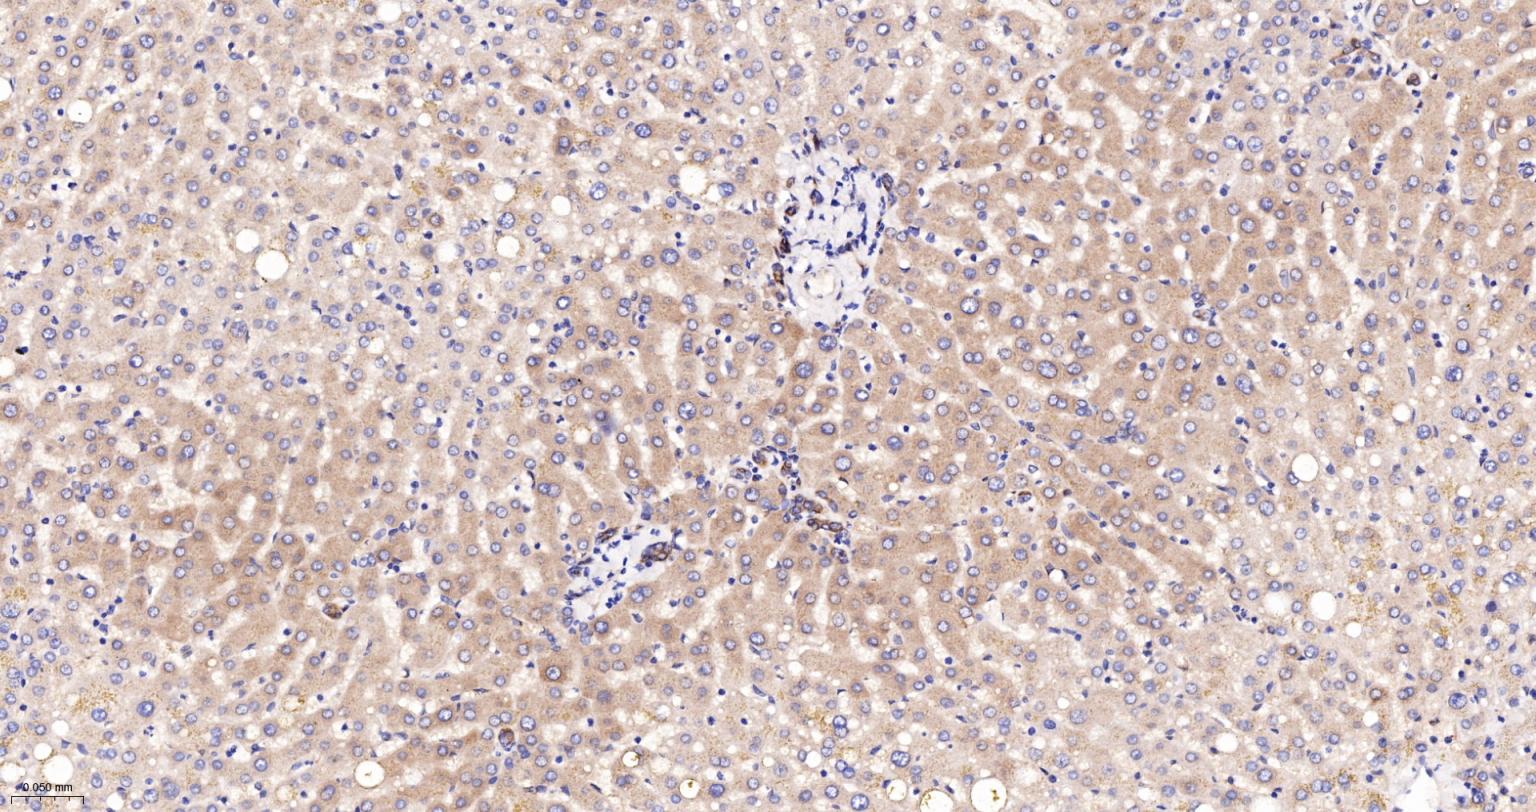

Paraformaldehyde-fixed, paraffin embedded Human Liver; Antigen retrieval by boiling in sodium citrate buffer (pH6.0) for 15 min; The section was incubated with Radixin Monoclonal Antibody, Unconjugated (bsm-61253R) at 1:200 overnight at 4°C, followed by conjugation to the bs-0295G-HRP and DAB (C-0010) staining.

Paraformaldehyde-fixed, paraffin embedded Rat Liver; Antigen retrieval by boiling in sodium citrate buffer (pH6.0) for 15 min; The section was incubated with Radixin Monoclonal Antibody, Unconjugated (bsm-61253R) at 1:200 overnight at 4°C, followed by conjugation to the bs-0295G-HRP and DAB (C-0010) staining.

Paraformaldehyde-fixed, paraffin embedded Mouse Liver; Antigen retrieval by boiling in sodium citrate buffer (pH6.0) for 15 min; The section was incubated with Radixin Monoclonal Antibody, Unconjugated (bsm-61253R) at 1:200 overnight at 4°C, followed by conjugation to the bs-0295G-HRP and DAB (C-0010) staining.